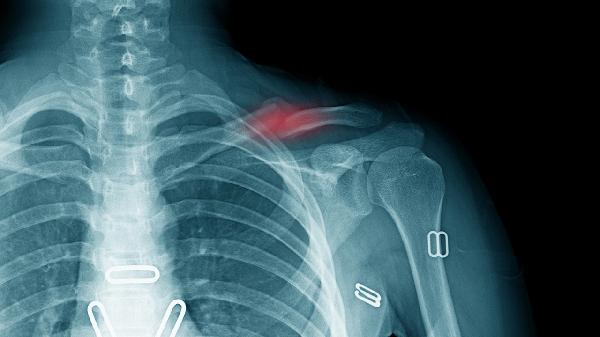

鎖骨骨折保守治療要多少錢

鎖骨骨折保守治療一般需要2000元到8000元,實際費用受到骨折類型、治療方案、地區(qū)差異、復(fù)查頻率、并發(fā)癥處理等多種因素的影響。

常規(guī)需3-5次X線復(fù)查每次約150-300元,若出現(xiàn)延遲愈合需增加復(fù)查次數(shù)。部分醫(yī)院會包含1-2次康復(fù)評估約200-500元/次,高齡患者可能需額外骨密度檢查約300元。